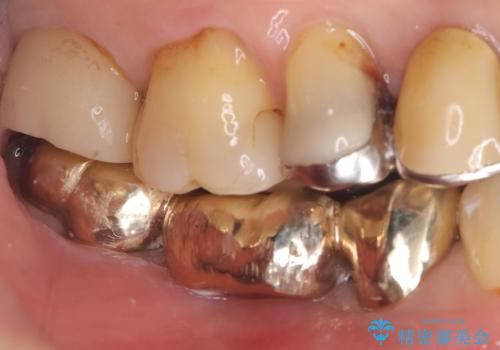

- 主訴:つい先日入れたセラミック(ジルコニア)ブリッジが奥歯部分で割れた。いつも同じ場所で壊れる。これで3度目。

セラミックに比べ、割れづらい金属(ゴールドでのブリッジのやり替えとなりました。

セラミックに比べ、破折リスクの少ない金属を使用したブリッジでのやり替えとなりました。

両支台歯が失活歯のため、どちらかもしくは両方の歯が破折した際、再度ブリッジを除去した治療が必要になるリスクとインプラント治療のご提案もさせていただきましたが、ブリッジでの治療を希望されました。

右下5番は支台歯CR築造を行っています。